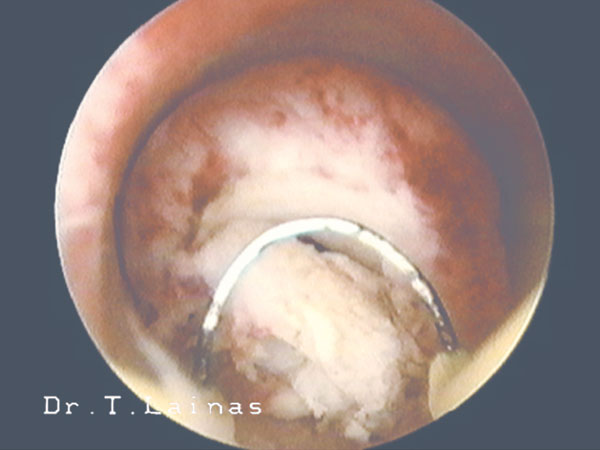

Η εφαρμογή της υστεροσκοπικής χειρουργικής αποτελεί τη σύγχρονη αντιμετώπιση των καλοηθών παθολογικών καταστάσεων της κοιλότητας της μήτρας και ιδιαίτερα αυτών που σχετίζονται με την υπογονιμότητα. Παράδειγμα υστεροσκοπικών επεμβάσεων αποτελούν η λύση ενδομητρικών και ενδοτραχηλικών συμφύσεων, η αφαίρεση πολυπόδων και υποβλεννογονίων ινομυωμάτων μήτρας και η διατομή διαφράγματος μήτρας.

Αρκετοί υποστηρίζουν ότι υπάρχει αύξηση των ποσοστών επιτυχίας κυήσεως μετά την υστεροσκοπική χειρουργική διόρθωση των καλοήθων παθολογικών καταστάσεων της μητριαίας κοιλότητας